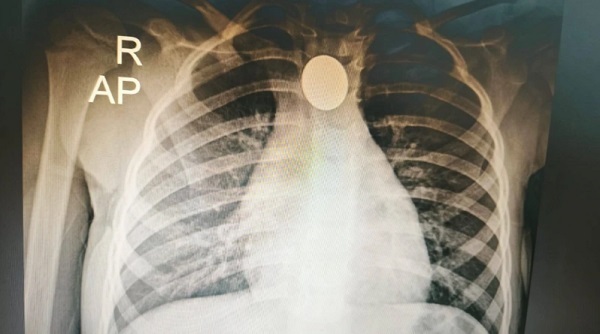

Exitosa extracción de moneda a niña de tres años en Ineram

Médicos del Ineram extrajeron una moneda a una niña de tres años mediante una técnica rápida y segura en Asunción. ...[Leer más]

Rápida intervención médica salva a niña de tres años que tragó una moneda

Una niña de tres años oriunda de Mariano Roque Alonso fue intervenida de urgencia tras tragar una moneda. El objeto extraño fue extraída exitosamente mediante esofagoscopía rígida en el INERAM. Los médicos destacaron la rapidez del procedimiento y reco... [Leer más]